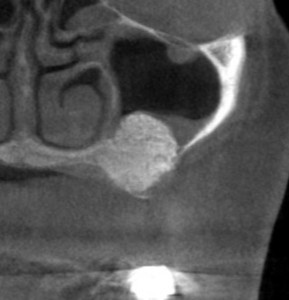

左臼歯に、3歯は必要と思われましたが、CTを見ると、1本目は骨の幅が狭く、2本目、3本目は骨の高さが足りません。

薄いところでは1mm程しかありませんでした(下の写真、2段目)。